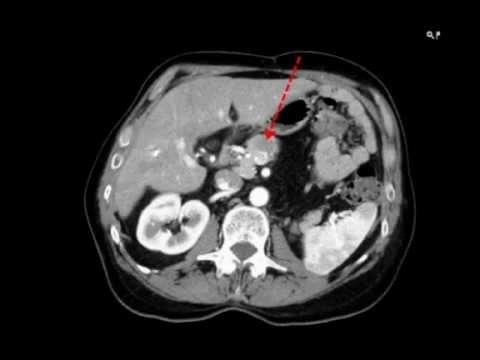

Customer testimonial by Dr. Enrique Castellanos regarding transrectal implantation of Gold Anchor fiducial markers in prostate to enable greater accuracy and precision in radiation therapy. Read more: @GoldAnchor